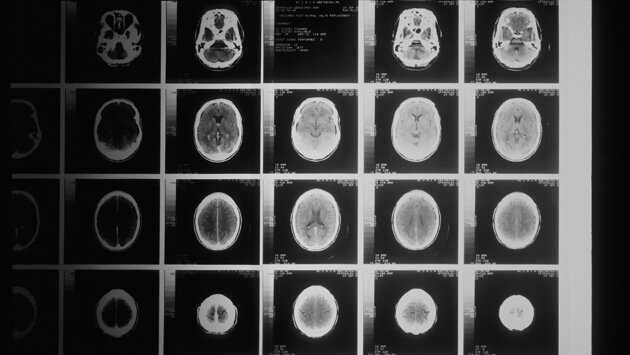

Как показало новое исследование, те, кто живёт в районах с низким социально-экономическим статусом, гораздо чаще страдают от инсульта, чем люди, которые живут в районах с более богатых районах. Об этом говорится в статье, опубликованной в Journal of Stroke and Cerebrovascular Diseases.

В рамках нового исследования учёные проанализировали записи больниц и смертей в Тасмании за период с 2007 по 2020 год. Они обнаружили, что у людей из группы с самым низким социально-экономическим статусом вероятность столкнуться с инсультом была на 33% выше, чем у тех, кто относился к группе с самым высоким социально-экономическим статусом.

Особую обеспокоенность вызывает факт, что влияние более низкого социально-экономического статуса на возникновение инсульта было сильнее выражено у молодых. Также исследование показало, что факторы риска инсульта, такие как диабет, высокое кровяное давление и болезни сердца, чаще встречаются в неблагополучных сообществах.